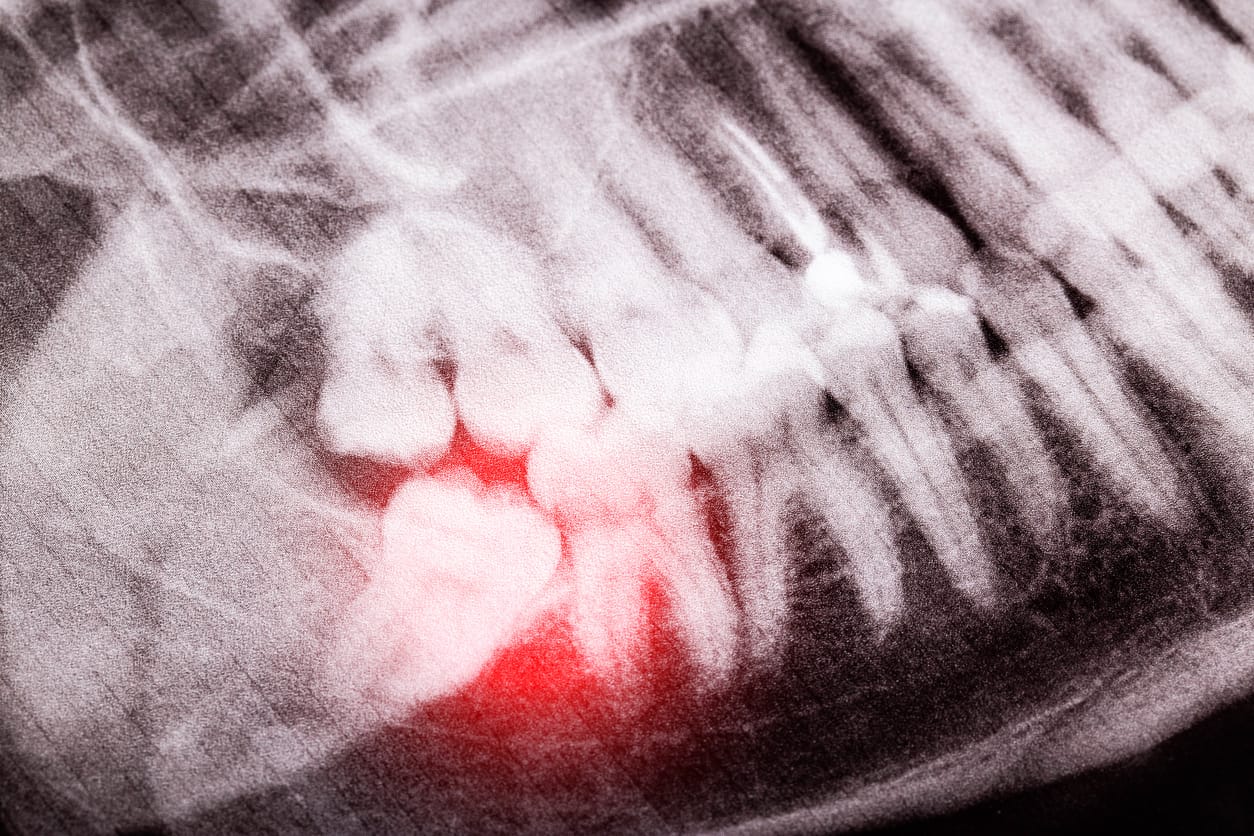

A coronectomy is a procedure that involves removing the crown of a lower wisdom tooth while keeping the roots behind in the bone. When a lower wisdom tooth becomes impacted (growing either sideways, horizontally, diagonally, forwards or backwards) problems can occur for the gum and surrounding teeth.

Often, removal of the wisdom tooth is the best option to protect the region from infection and damage. However, lower wisdom teeth can lie extremely close to the inferior alveolar nerve. This nerve supplies the lower lip with sensory sensation. There is a risk of damaging this nerve when extracting a lower wisdom tooth.